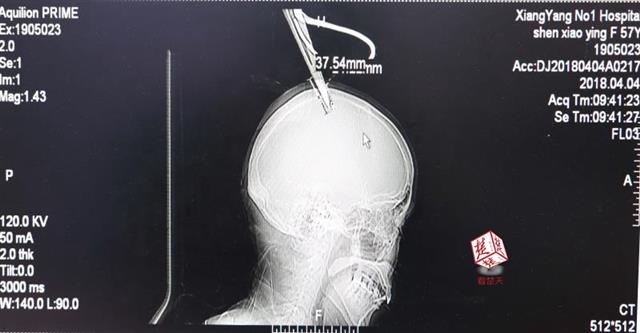

醫(yī)生檢查發(fā)現,剪刀刀尖斜嵌在沈某顱骨里,離腦髓只有兩三毫米。所幸是斜著插進去,如果是垂直刺入,很有可能造成癱瘓。

4月4日清晨,襄陽市樊城區(qū)太平店鎮(zhèn)57歲的農村婦女沈某,在采摘香椿嫩芽時,綁在竹桿上的剪刀因竹子腐朽不慎折斷,剪刀斜插入頭顱。經過及時搶救,目前脫離生命危險。

醫(yī)生檢查發(fā)現,剪刀刀尖斜嵌在沈某顱骨里,離腦髓只有兩三毫米。所幸是斜著插進去,如果是垂直刺入,很有可能造成癱瘓。最終經過手術,剪刀被取出,沈某目前仍在ICU進一步觀察。